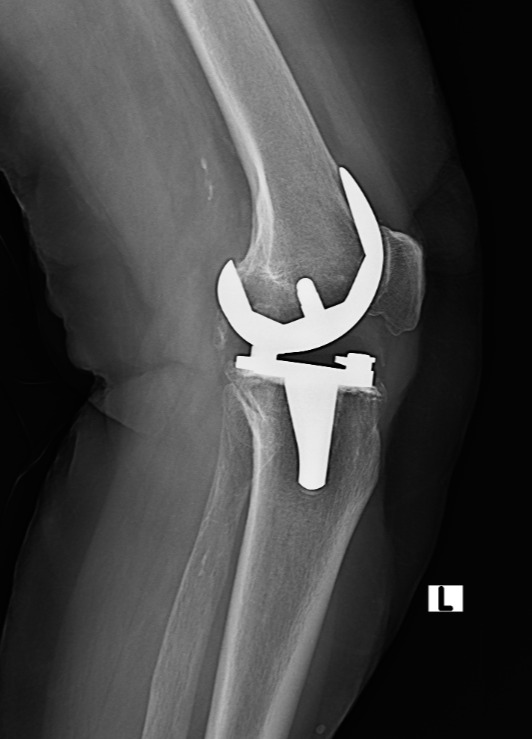

Eklem protez cerrahisi (artroplasti), halk arasında “eklem protezi” olarak bilinir. En çok kireçlenen eklem ve en çok protez uygulanan eklem diz eklemidir. Bunun ardından Kalça eklemi gelir. Ayrıca omuz, ayak bileği ve el bileği eklemlerinde de kireçlenme yani artroz sonrası eklem protez cerrahisi uygulanmaktadır. Eklemlerimiz zamanla yıpranabilir veya kireçlenme nedeniyle görevini yapamaz hale gelebilir. Bunun birçok sebebi vardır. Bu durumda protez cerrahisi sayesinde ağrısız hareket etmek, günlük hayata geri dönmek mümkündür. Türkiye'de protez cerrahisi 90'lı yıllarda İstanbul, İzmir ve Ankara gibi illerde yapılırken şu an her şehirde yapılabilmektedir. Ege Üniversitesi'nde diz protezi ve kalça protezleri konusunda 40 yıllık deneyimi olan Hakkı Sur ile eğitim aldıktan sonra Fransa'da yine ünlü protez merkezinde birçok vakaya katılmış ve yapmış olmanın bu cerrahideki önemini meslek hayatımda daha da idrak ettim.

Klinik uygulamada protez olan hasta ameliyat sonrası ilk günde ayağa kaldırılmaktadır. Yatak içi ve yatak kenarında fizik tedavi hareketleri yapılmaktadır. 2. gün hastanın hareket açıklığı artırılmaktadır. 3. günde ise fizyoterapistler eşliğinde merdiven inip çıkma egzersizleri öğretilmektedir. Hasta evine giderken sondası çıkmış ve tuvalete gidebilecek şekilde plan yapmaktayız. Dikişler için 15 gün sonra kontrole gelen hasta tekrar değerlendirilmektedir.